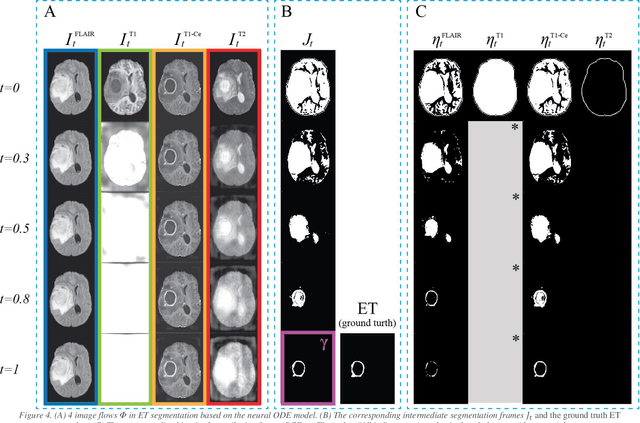

Abstract:Purpose: To develop a neural ordinary differential equation (ODE) model for visualizing deep neural network (DNN) behavior during multi-parametric MRI (mp-MRI) based glioma segmentation as a method to enhance deep learning explainability. Methods: By hypothesizing that deep feature extraction can be modeled as a spatiotemporally continuous process, we designed a novel deep learning model, neural ODE, in which deep feature extraction was governed by an ODE without explicit expression. The dynamics of 1) MR images after interactions with DNN and 2) segmentation formation can be visualized after solving ODE. An accumulative contribution curve (ACC) was designed to quantitatively evaluate the utilization of each MRI by DNN towards the final segmentation results. The proposed neural ODE model was demonstrated using 369 glioma patients with a 4-modality mp-MRI protocol: T1, contrast-enhanced T1 (T1-Ce), T2, and FLAIR. Three neural ODE models were trained to segment enhancing tumor (ET), tumor core (TC), and whole tumor (WT). The key MR modalities with significant utilization by DNN were identified based on ACC analysis. Segmentation results by DNN using only the key MR modalities were compared to the ones using all 4 MR modalities. Results: All neural ODE models successfully illustrated image dynamics as expected. ACC analysis identified T1-Ce as the only key modality in ET and TC segmentations, while both FLAIR and T2 were key modalities in WT segmentation. Compared to the U-Net results using all 4 MR modalities, Dice coefficient of ET (0.784->0.775), TC (0.760->0.758), and WT (0.841->0.837) using the key modalities only had minimal differences without significance. Conclusion: The neural ODE model offers a new tool for optimizing the deep learning model inputs with enhanced explainability. The presented methodology can be generalized to other medical image-related deep learning applications.